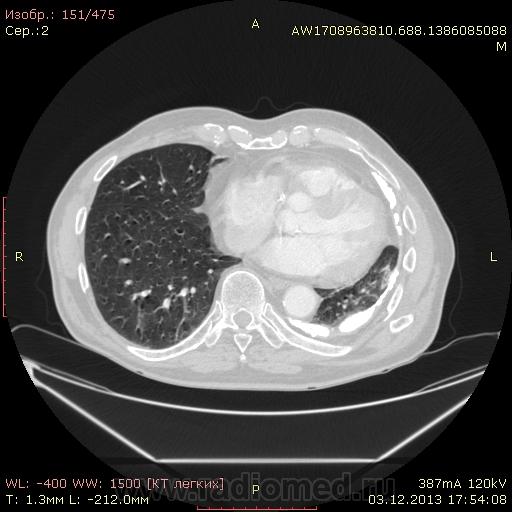

Доброго времени суток уважаемые форумчани! :)Провели исследование КТ грудной клетки с контрастированием, для выявления аневризмы грудного отдела аорты. В результате увидели это:

??? Аневризму честно не вижу (мало опыта в определении аневризм). Тромбоз в бассейне верхней полой вены. В левом легком обызвествленные плевральные шварты? как исход осумкованного плеврита неизвестной давности?

Ребята, вы что, какая жидкость? Чистая известь, посмотрите в костном окне. Отставить натив (в данном случае, хотя для аневризм он обычно нужен). Отставить тромбоз верхней полой вены (потоковые артефакты, не дело вены в артериальную фазу оценивать). Отставить аневризму  аорты, поперчник восходящего отдела на уровне легочного ствола 42мм. А вот легочная гипертензия, здравствуй: поперечник легочного ствола - 37мм, ПЛА - 25мм, ЛЛА - 25мм, НАо - 25-34мм.

Для справки: холестериновые камни имеют плотность менее 100 ед.Н. Имеющаяся хренотень в левом гемитораксе имеет плотность больше костной, до 1500 ед.Н. Вопрос: какая химико-физико-биологическая реакция может способствовать превращению мягинькаво холестерина в термоядерную плевральную лепёшку?)